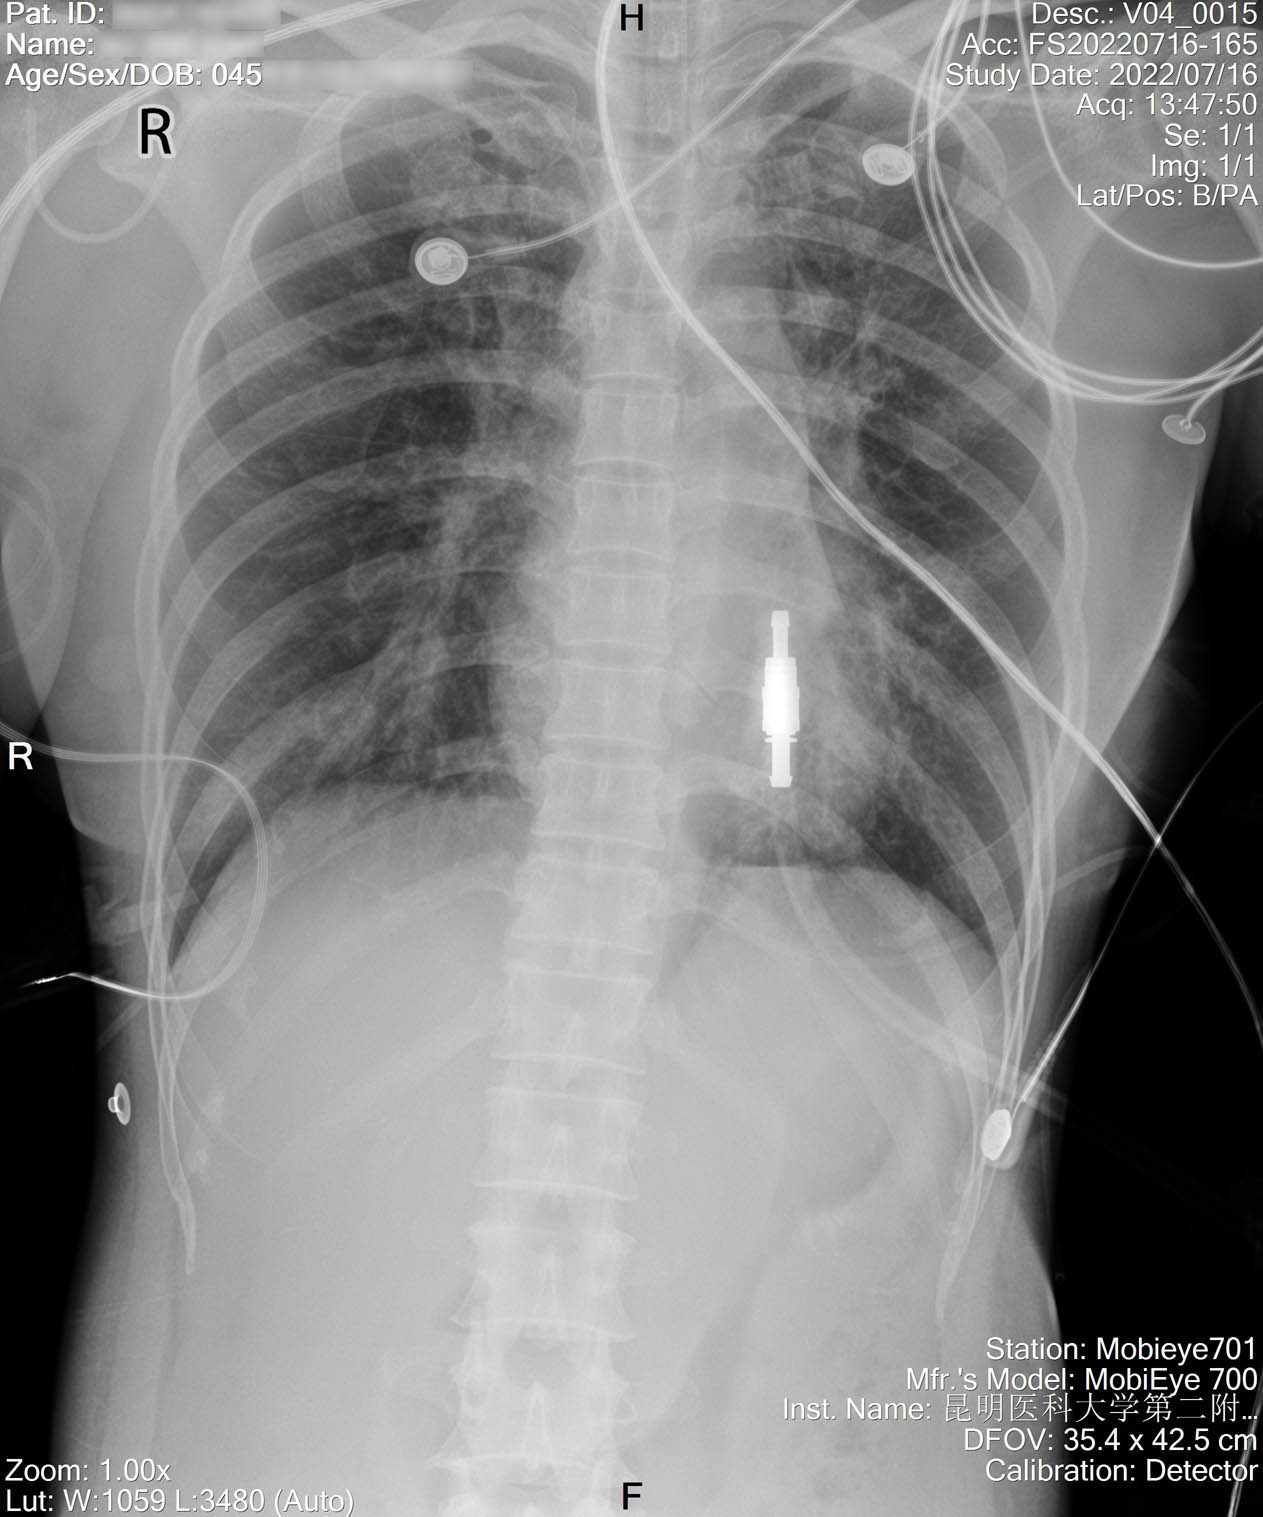

1.2.156.112536.2.560.184134135149163099.1425263277683.6.jpg

2022-07-19_胸片